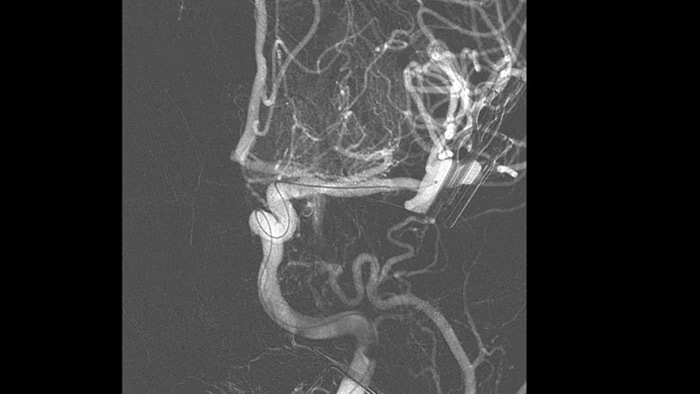

SmartCT Vaso IV

Comprobar la ubicación y la longitud del coágulo

SmartCT Vaso permite la visualización más allá del coágulo con imágenes periprocedimiento de las caras distales de los vasos en el accidente cerebrovascular isquémico. SmartCT Vaso es una técnica de adquisición basada en una TC de haz cónico y una inyección de contraste intrarterial. Permite la visualización más allá del coágulo con imágenes periprocedimiento de las caras distales de los vasos en el accidente cerebrovascular isquémico. Mediante el llenado retrógrado, se ven las estructuras de los vasos antes y después del coágulo. SmartCT Vaso 3D Roadmap puede utilizarse para visualizar los dispositivos de recuperación de coágulos.

Las referencias anatómicas apoyan una navegación 3D precisa

SmartCT image

SmartCT Roadmap proporciona referencias anatómicas para apoyar la navegación precisa de la aguja guía, el catéter y el dispositivo al coágulo.